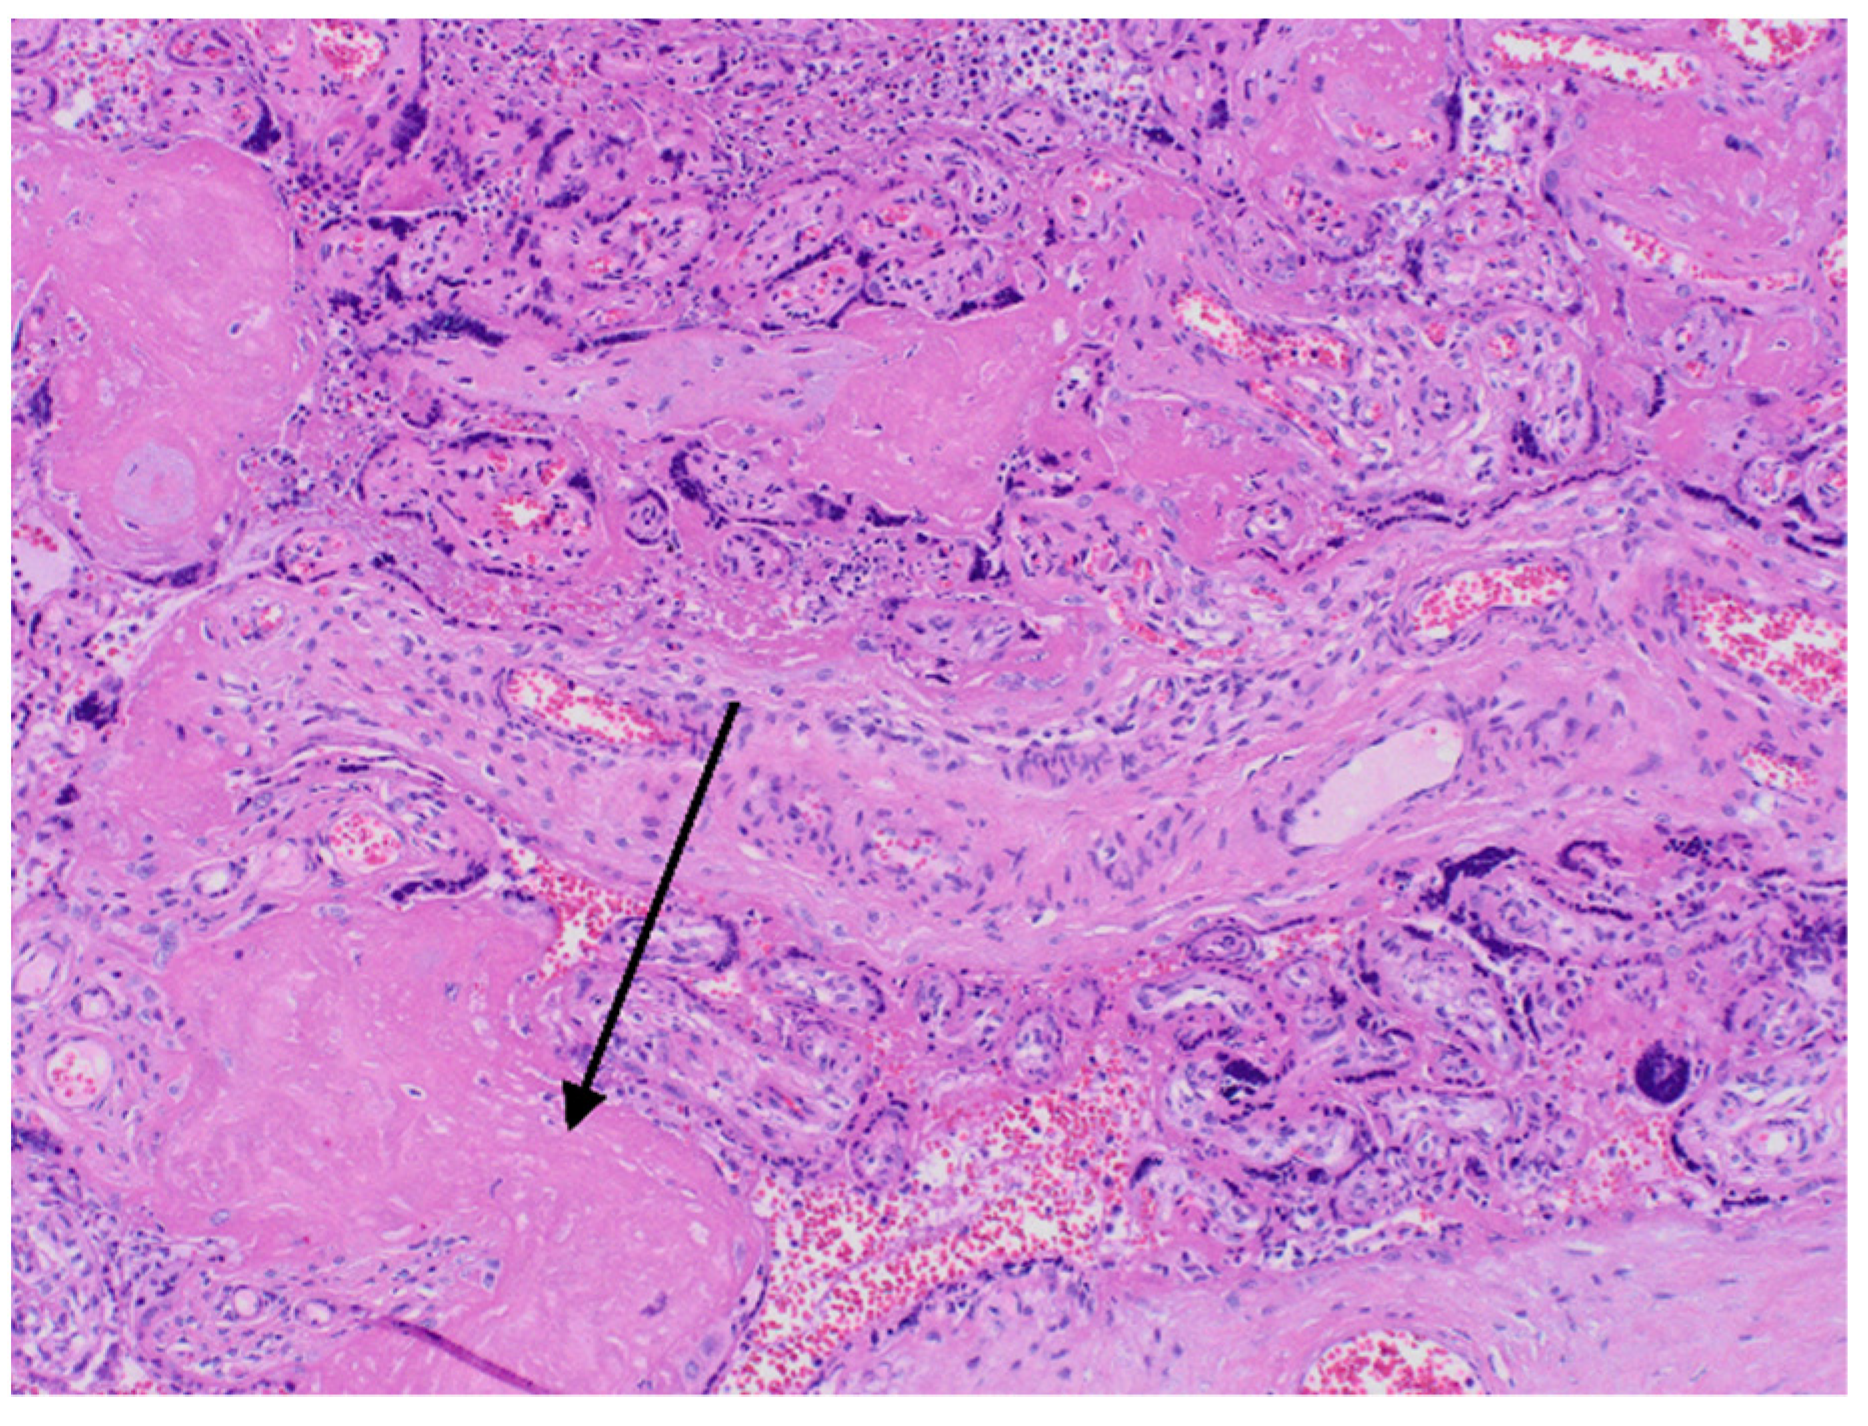

The results of neonatal examinations are summarised in Table 2. Significant changes of D-dimers, fibrinogen, AST were observed. Arterial blood gas test showed: pH 6.618 N: 7.35–7.45), pO2 64.9 mmHg (N: 50–70), pCO2 71.8 mmHg (N: 45–55), cLac-30 mmol/L (N: <2). The results indicated a significant metabolic acidosis, chronic hypoxia and coagulation disorders. Brain ultrasound revealed increased diffuse echogenicity of brain tissue, scanty, high-resistance blood flow. Abdominal ultrasound showed abnormal renal and visceral blood flow. At the same time, anuria, hypoglycaemia and hypotension persisted. The newborn did not respond to the treatment and succumbed 24 h after birth. In the postmortem examination congestion of the entire brain, especially the choroid plexus, the central area around the ventricles, and the meninges was found. The image suggested blockage of the venous outflow. Early, diffuse ischaemic changes with the necrosis in the cerebral cortex, as well as blood clots in small vessels in the brain were visualised. The newborn’s lungs were also congested, with foci of atelectasis. The postpartum histopathology examination revealed a strongly hyperaemic placenta with small infarcts and abundant fibrin deposits (chronic intervillositis) (Figure 2 and Figure 3).

Figure 3.

Histopatological images. Arrow—fibrin deposits.

The severe course of SARS-CoV-2 infection in pregnancy increases the prothrombotic potential also in the foetal part of the placenta. Postpartum histopathology tests showed the presence of infarction foci and inflammatory infiltrates. Recently, a meta-analysis was published comparing the histopathology examinations of the placenta of pregnant patients with high-risk pregnancy and the placenta of patients with pregnancy complicated by COVID-19 infection. The meta-analysis showed a significant reduction in vascular perfusion, foci of acute and chronic inflammation, foci of thrombosis, areas of fibrin deposits [26,27]. This means that the risk of stillbirth by the COVID positive patient is much higher than in the general population. Similar changes were described in the histopathology examination of the placenta of the presented patients.